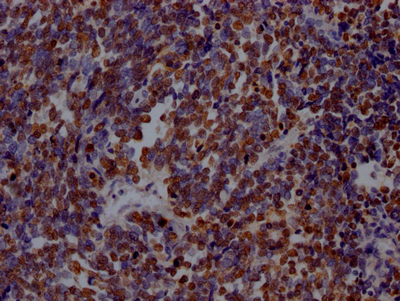

IHC image of CSB-RA160472A0HU diluted at 1:100 and staining in paraffin-embedded human lung cancer performed on a Leica BondTM system. After dewaxing and hydration, antigen retrieval was mediated by high pressure in a citrate buffer (pH 6.0). Section was blocked with 10% normal goat serum 30min at RT. Then primary antibody (1% BSA) was incubated at 4℃ overnight. The primary is detected by a Goat anti-rabbit IgG polymer labeled by HRP and visualized using 0.05% DAB.